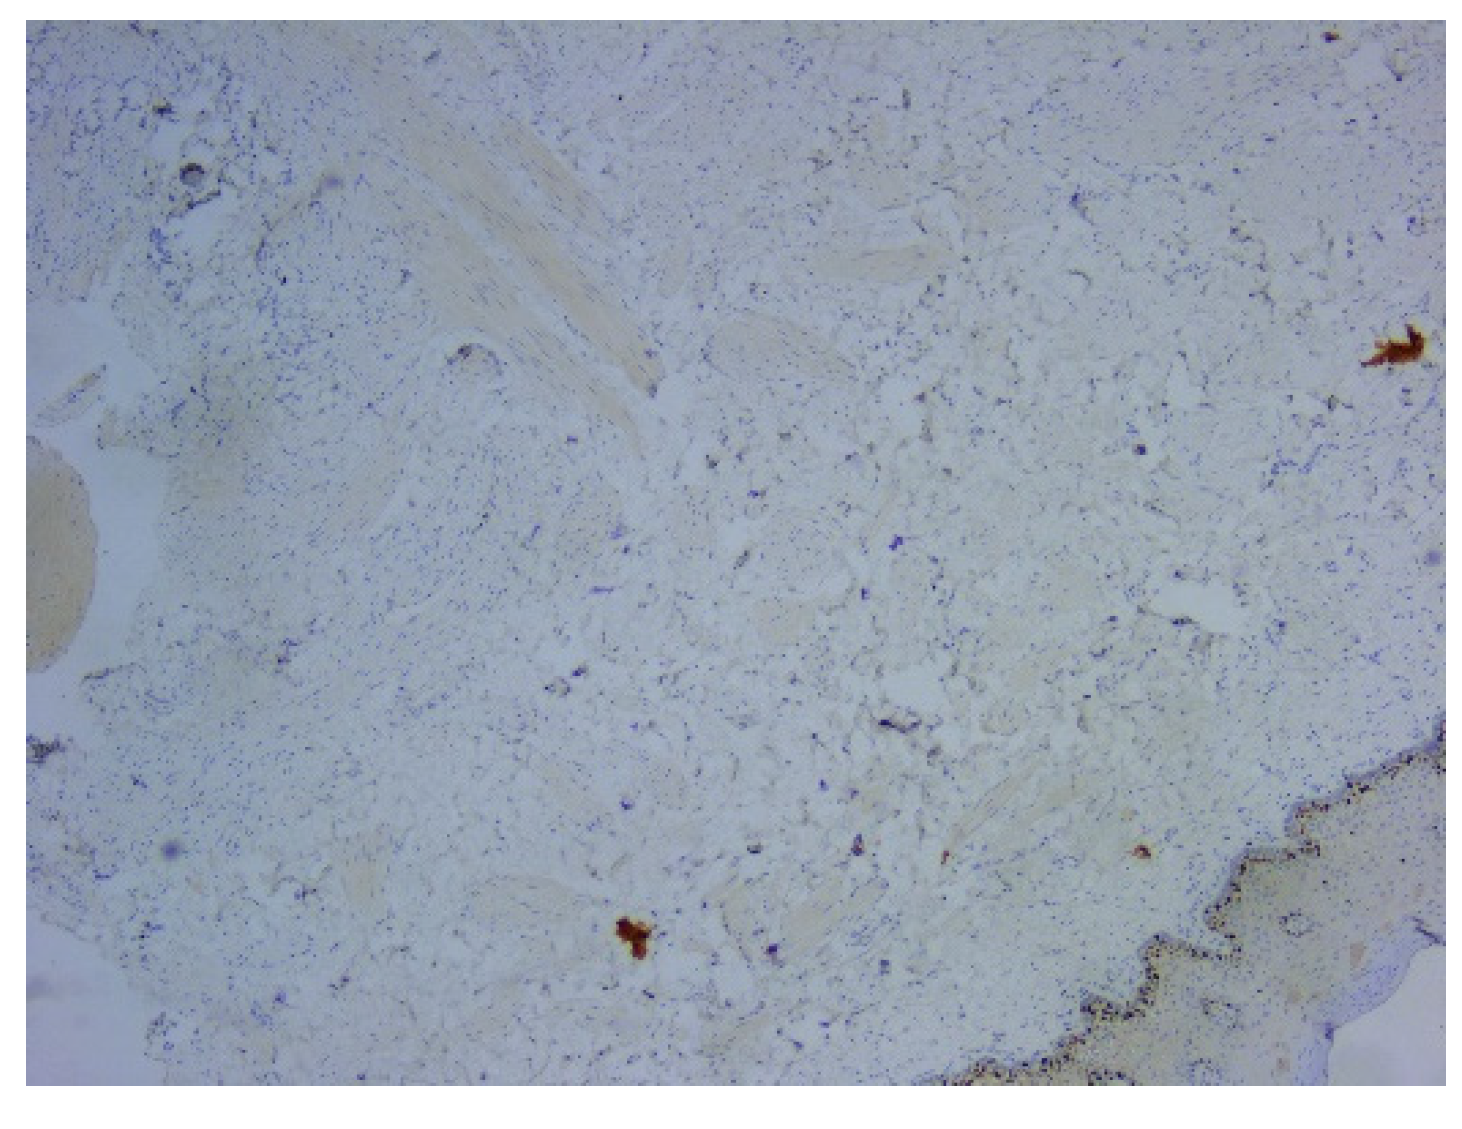

On microscopic examination of Hematoxylin–Eosin (HE) stained slides, there were observed fascicles of spindle-shaped cells arranged in unequal bundles, with large eosinophilic cytoplasm and vesicular, monotonous, blunt-ended nuclei, with finely granular chromatin (Figure 3). Immunohistochemically (IHC) intense and diffuse positive reactions were found for desmin (Figure 4), as well as for smooth muscle actin (SMA) (Figure 5). On the other hand, there were immunohistochemically negative tumor cells for vimentin staining, with positive internal control at the level of the vascular component (Figure 6). Ki67 cell proliferation index was 3% (Figure 7). The final diagnosis was of leiomyoma.

Figure 6. Microscopic image using immunohistochemical reactions for vimentin: (a) Negative IHC reaction for vimentin, with positive control, Anti-Vimentin Antibody, ob. 5x; (b) Immunohistochemically negative tumor cells for vimentin, positive internal control at the level of the vascular component, Anti-Vimentin Antibody, ob. 20x.